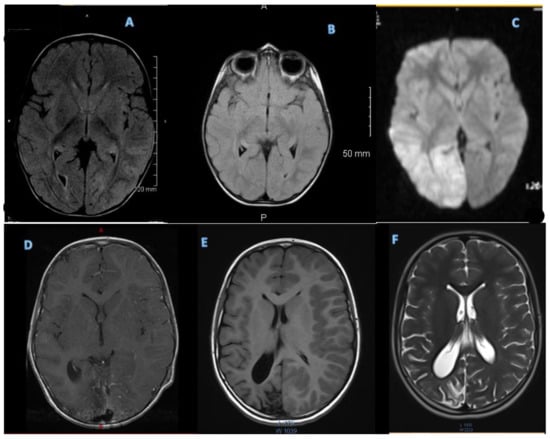

3.2.2. MRI

An initial MRI was performed during the first severe attack at age 21 months, and it was suspicious for encephalitis. Subsequent MRIs were performed at every severe HM event, one outside of the HM event, and rapid sequences or abbreviated MRIs at minor HM events (Figure 2).

Figure 2. (A) Two years and 4 months (3rd attack—1st with hemiplegia) showed medial left temporal lobe edema (FLAIR imaging). (B) Two years and 5 months (no attack) normal (FLAIR imaging). (C) Diffusion-weighted imaging (DWI) at 3 years 9 months during 4th attack HM episode, showing increased signal in right occipital lobe. (D) Contrast-enhanced TI imaging at 4 years showing increased enhancement in right occipital lobe during 5th HM episode. (E) TI imaging at 7 years during 6th attack showing atrophy in right occipital lobe. (F) T2 imaging performed at 11 years during minor HM episode, demonstrating stable atrophy on the right occipital lobe without associated edema.